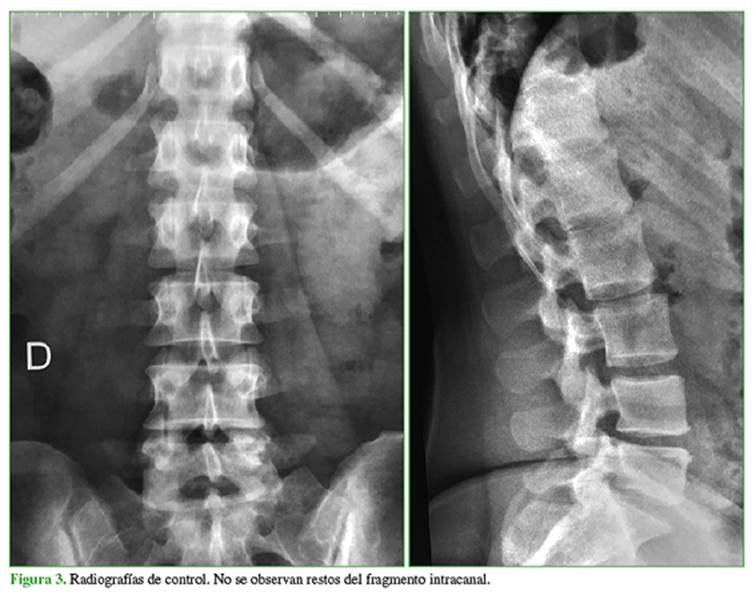

En las radiografías y las imágenes de la resonancia magnética y la tomografía computarizada tridimensional de la columna dorsolumbar, se observó un cuerpo extraño en T12-L1, paracentral derecho, cercano al foramen homolateral, que se interpretó como un resto de aguja que se había roto en el momento de la punción raquídea para la cesárea, seis meses atrás (Figura 1).

Los estudios diagnósticos más útiles son la radiografía y la tomografía computarizada que muestran el fragmento metálico de la aguja. Staats y cols. publican un caso de aguja intracanal que no se había observado claramente en las imágenes iniciales por resonancia magnética, por lo que el diagnóstico debió completarse con una tomografía computarizada.9 En nuestra paciente, la resonancia mostró un artefacto en la zona del canal raquídeo, compatible con un cuerpo extraño, que se confirmó con el estudio tomográfico.